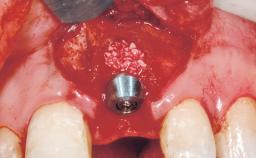

Immediate Flapless Placement of an Implant in a Maxillary Left Central Incisor Site

A 42-year-old female patient was referred to our clinic at the School of Dentistry of the University of São Paulo in November 2004, presenting a deficient restoration in the upper left central incisor. The clinical examination revealed no gingival retraction or any signs of gingival inflammation and, therefore, previous periodontal treatment was not considered. The patient presented a high lip line at full smile and a thin tissue biotype. This combination characterized a high-risk situation from an anatomic point of view, which required careful preoperative planning and cautious surgical execution.

| Placement Protocol | Immediate implant placement |

| Tooth Site | Maxillary incisor or canine |

| Socket Morphology | Single-root socket |

| Socket Integrity | Sufficient, with intact bone walls |